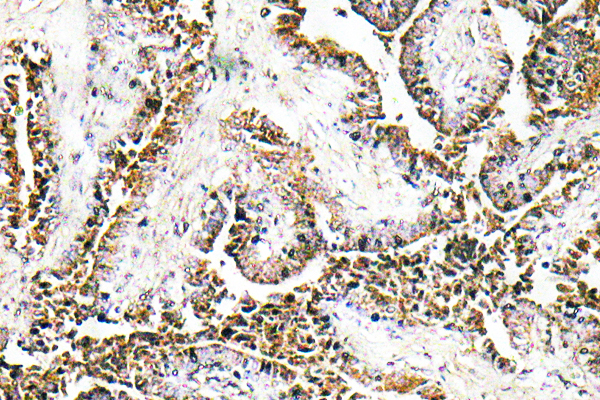

ApplicationsELISA, ImmunoHistoChemistry

ApplicationsELISA, ImmunoHistoChemistry

ApplicationsWestern Blot, ELISA, ImmunoHistoChemistry

ApplicationsELISA, ImmunoHistoChemistry

ApplicationsELISA, ImmunoHistoChemistry

ApplicationsELISA, ImmunoHistoChemistry

ApplicationsELISA, ImmunoHistoChemistry

ApplicationsELISA, ImmunoHistoChemistry

ApplicationsELISA, ImmunoHistoChemistry

ApplicationsELISA, ImmunoHistoChemistry

ApplicationsELISA, ImmunoHistoChemistry

ApplicationsELISA, ImmunoHistoChemistry